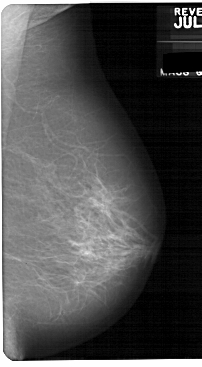

A_1726_1.RIGHT_MLO

RIGHT_MLO LINES 5491 PIXELS_PER_LINE 3016 BITS_PER_PIXEL 12 RESOLUTION 43.5 NON_OVERLAY